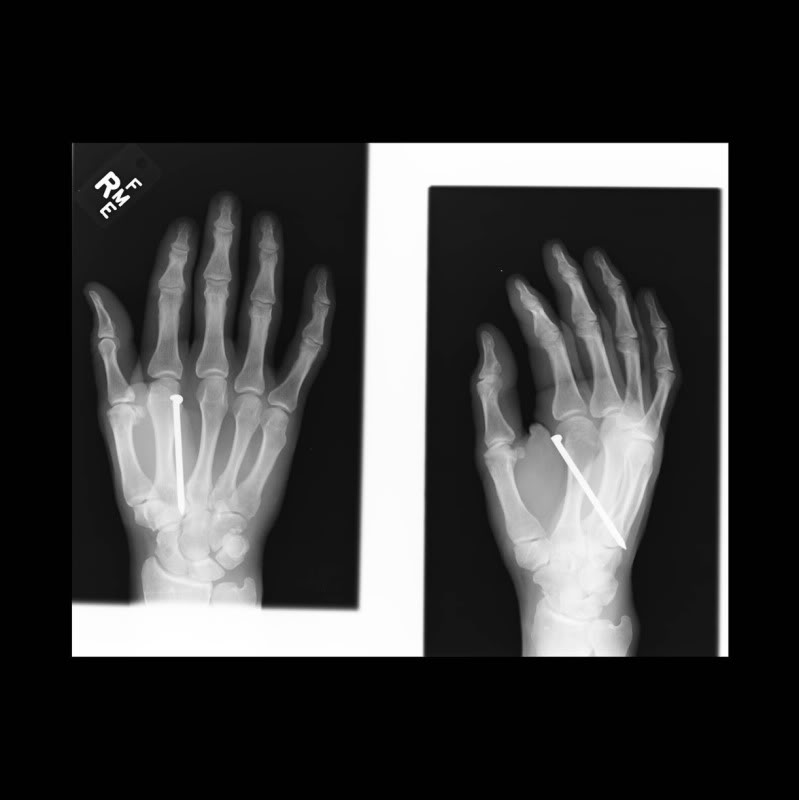

I like that dually.View attachment 184305 View attachment 184306 Picked up these two crème puffs yesterday.

Did it hurt?

It really didn't hurt........ " It was all meat somehow, no bones, tendons, muscles, etc. "